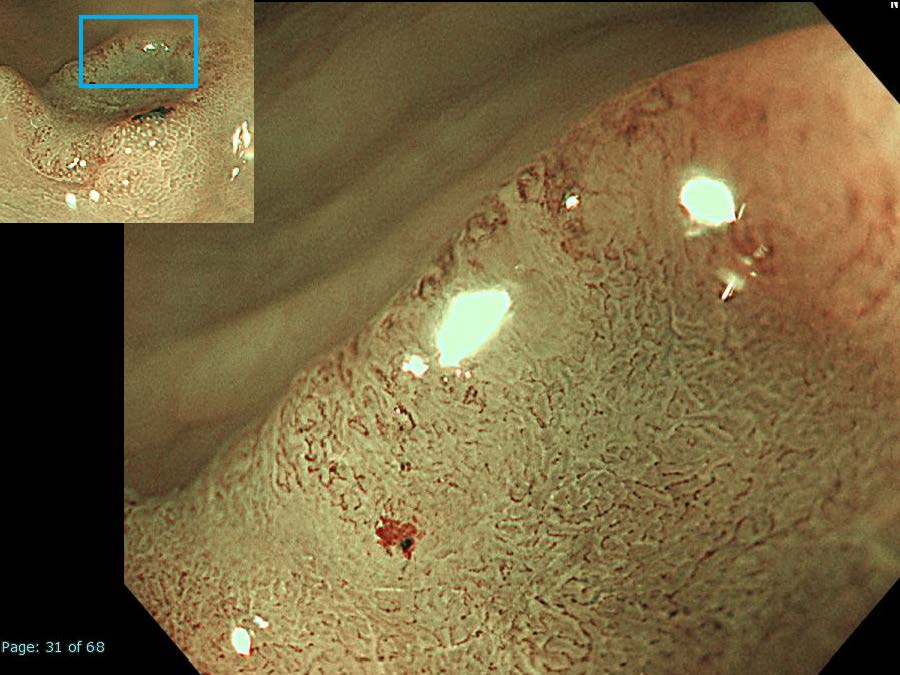

消化管Mapping~大腸~ 2021.10.27

消化管Mapping~大腸~

内視鏡検査・治療

消化管Mapping